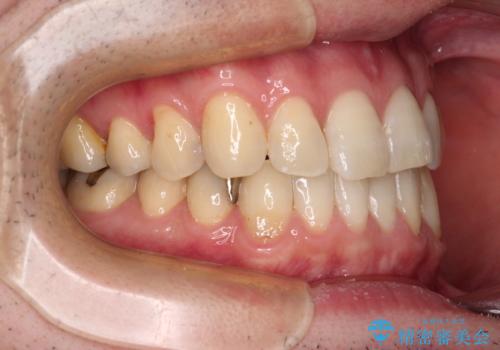

欠損のある歯列 インビザラインで整った歯並びに

- デコボコした前歯をセラミックできれいに揃えたいとのことで来院された患者様です。

歯を削って整えることは簡単ですが、健全な歯を削って後悔してからでは遅いため、矯正治療を提案しました。

はじめは矯正治療の期間が長いことに悩んでいらっしゃいましたが、ある程度整えば満足するだろうとのことで、インビザラインにて矯正治療を行うこととしました。

左上の犬歯が欠損しているため、正中の位置や奥歯の咬み合わせが理想的にならない点を了承していただきました。